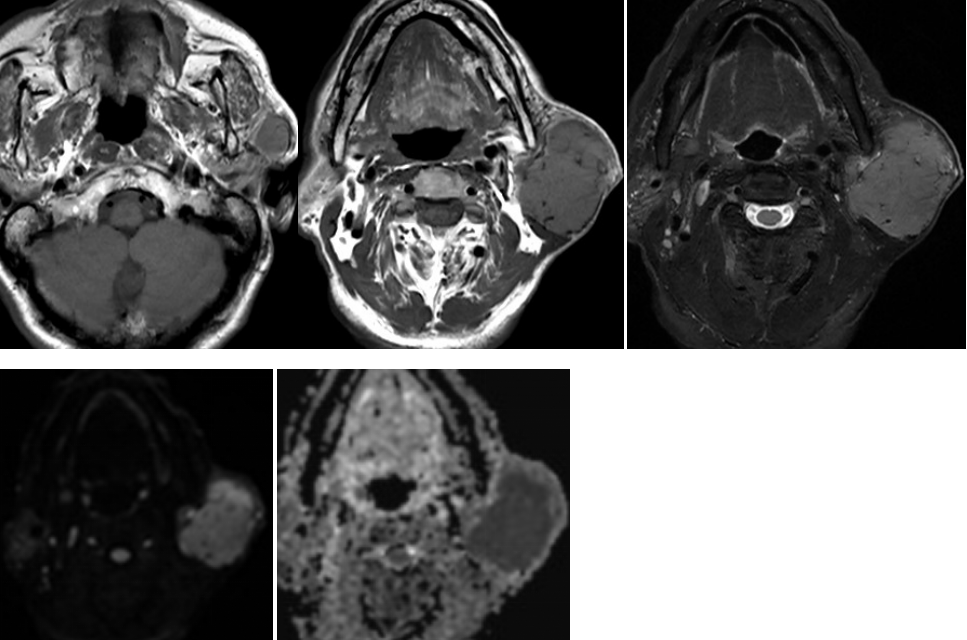

本院病例(多形性腺瘤):患者,男性,37岁,发现右侧腮腺包块半年余,无疼痛、发热症状;右侧腮腺区分叶状囊实性肿块,T2WI明显高信号,T1WI低信号,无明显弥散受限,增强明显不均匀强化。